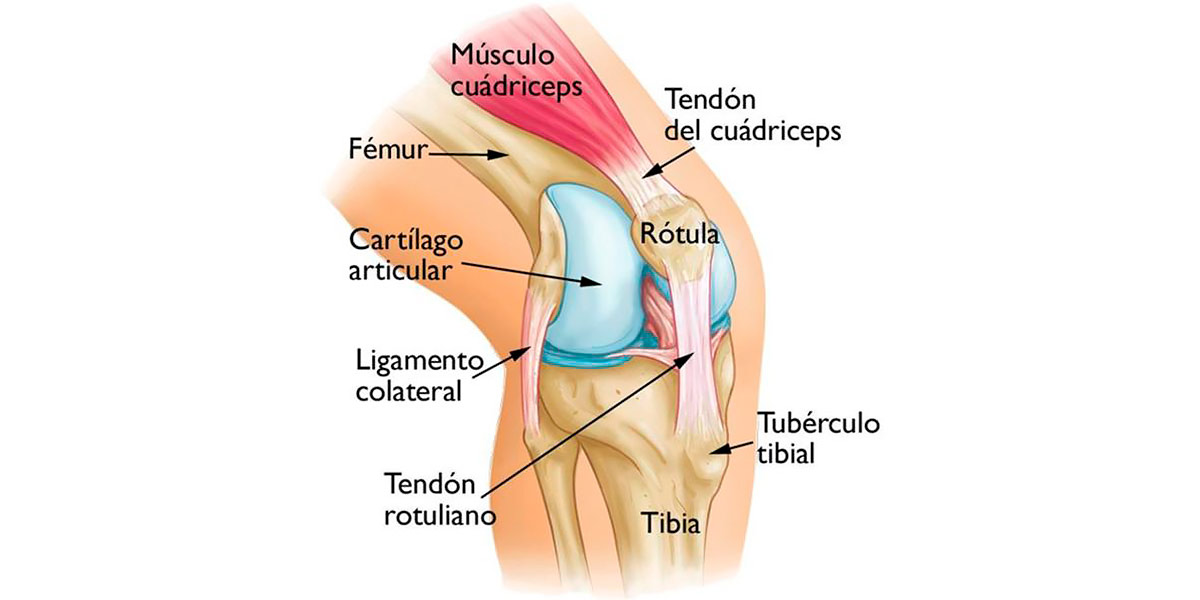

O joelho de corredor é uma denominação coloquial do síndrome femuropatelar, uma alteração na estrutura do joelho que leva à degradação da cartilagem das articulações e causa dores, devido ao atrito entre a rótula e o fémur na flexo-extensão da articulação.

O joelho é uma estrutura complexa articular sinovial (diartrose) que possui grande mobilidade.

Figura I. Estrutura osteomioarticular do joelho.

Esta é a principal causa por ser uma articulação que provoca grandes problemas.

Como seres humanos, caminhamos em bipedestação, pelo que os membros inferiores se encontram em constante movimento e tensão, recebendo impactos de forma sistemática. O joelho liga o fémur à tíbia e ao perónio, e como ligação de ambos os segmentos ósseos, recebe uma grande carga em atividades diárias (caminhar, subir escadas, praticar exercício físico…)